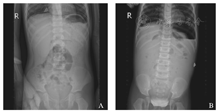

我院胃肠外科自2016年9月14日至2017年6月20日共收治3例口服布洛芬致十二指肠穿孔病例,其中女1例、男2例,年龄分别为2岁9个月、3岁、5岁,起病前均有上呼吸道感染高热超过39 ℃,为退热皆于起病前24~48 h内反复口服布洛芬5~8次,且均有2次服药间隔<4 h情况,其中2例更是有发热即口服,反复一夜4~5次,而说明书指示需间隔4~6 h方可再次服用,24 h服药次数不超过4次。而后才出现腹痛,即先发热后腹痛。3例患儿既往均无反复腹痛、反酸、呃逆、食欲欠佳病史,无消化性溃疡家族史。临床表现以腹痛、呕吐为主,其中1例患儿腹胀明显,均有腹膜刺激征,腹平片其中2例少量气腹,另1例大量液气腹,见图1。术前B超均无阳性提示。2例少量气腹患儿生命体征平稳,无休克表现,另1例大量液气腹患儿术前于急诊科即有休克,需抢救气管插管维持。

A.膈下少量游离气体;B.大量液气腹